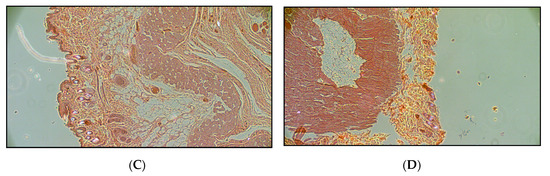

Development and Evaluation of a Human Skin Equivalent in a Semiautomatic Microfluidic Diffusion Chamber

by Júlia Tárnoki-Zách, Elod Mehes, Zsófia Varga-Medveczky, Dona Greta Isai, Nandor Barany, Edina Bugyik, Zsolt Revesz, Sándor Paku, Franciska Erdo and Andras Czirok

Pharmaceutics 2021, 13(6), 910; https://doi.org/10.3390/pharmaceutics13060910 - 20 Jun 2021

There is an increasing demand for transdermal transport measurements to optimize topical drug formulations and to achieve proper penetration profile of cosmetic ingredients. Reflecting ethical concerns the use of both human and animal tissues is becoming more restricted. Therefore, the focus of dermal [...] Read more.

There is an increasing demand for transdermal transport measurements to optimize topical drug formulations and to achieve proper penetration profile of cosmetic ingredients. Reflecting ethical concerns the use of both human and animal tissues is becoming more restricted. Therefore, the focus of dermal research is shifting towards in vitro assays. In the current proof-of-concept study a three-layer skin equivalent using human HaCaT keratinocytes, an electrospun polycaprolactone mesh and a collagen-I gel was compared to human excised skin samples. We measured the permeability of the samples for 2% caffeine cream using a miniaturized dynamic diffusion cell (“skin-on-a-chip” microfluidic device). Caffeine delivery exhibits similar transport kinetics through the artificial skin and the human tissue: after a rapid rise, a long-lasting high concentration steady state develops. This is markedly distinct from the kinetics measured when using cell-free constructs, where a shorter release was observable. These results imply that both the established skin equivalent and the microfluidic diffusion chamber can serve as a suitable base for further development of more complex tissue substitutes. Full article